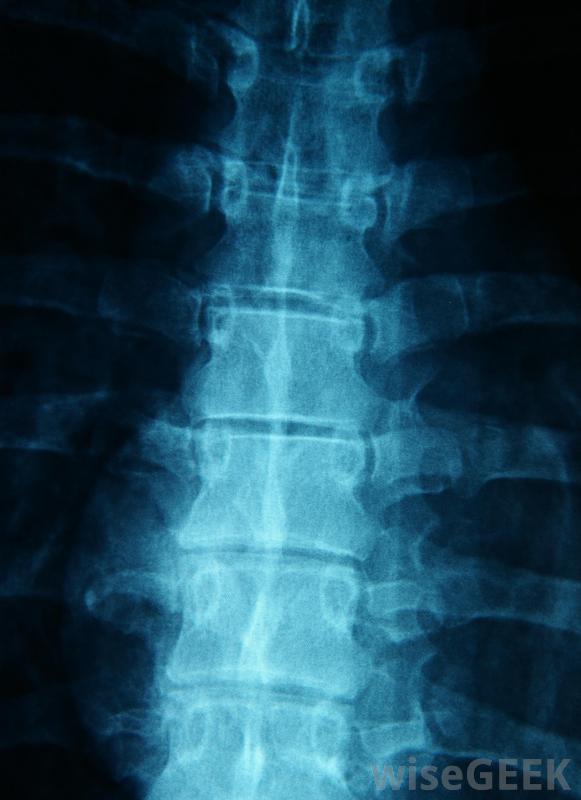

在医院里,可以佩戴背带,医生可以对背部进行x光和计算机断层扫描,以寻找胸部压缩性骨折的迹象。医生还会进行彻底的身体检查,以确定患者是否感到麻木、刺痛、虚弱,或认知障碍。根据患者的情况和事故中可能发生的任何其他伤害,专家可能需要提供紧急药物和治疗,以稳定呼吸、生命体征和意识。

脊柱的X光片将用于帮助诊断胸部压缩性骨折。